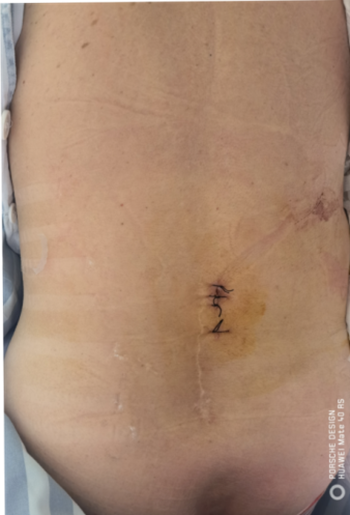

常规腰椎融合手术切口 UBE技术腰椎融合切口

UBE椎管减压术后小切口